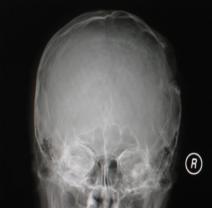

头颅CT和MRI可见颅骨缺损区下方软脑膜囊肿、脑软化灶或脑室穿通畸形(图2)。

图2:①和②CT及骨窗相显示右顶部颅骨缺损,其下方脑组织呈低密度改变;③-⑥MRI右顶局部颅骨缺如,脑组织轻度向外膨隆,右顶叶侧脑室体部旁局部脑组织缺如,代之以囊性长T1、长T2信号。